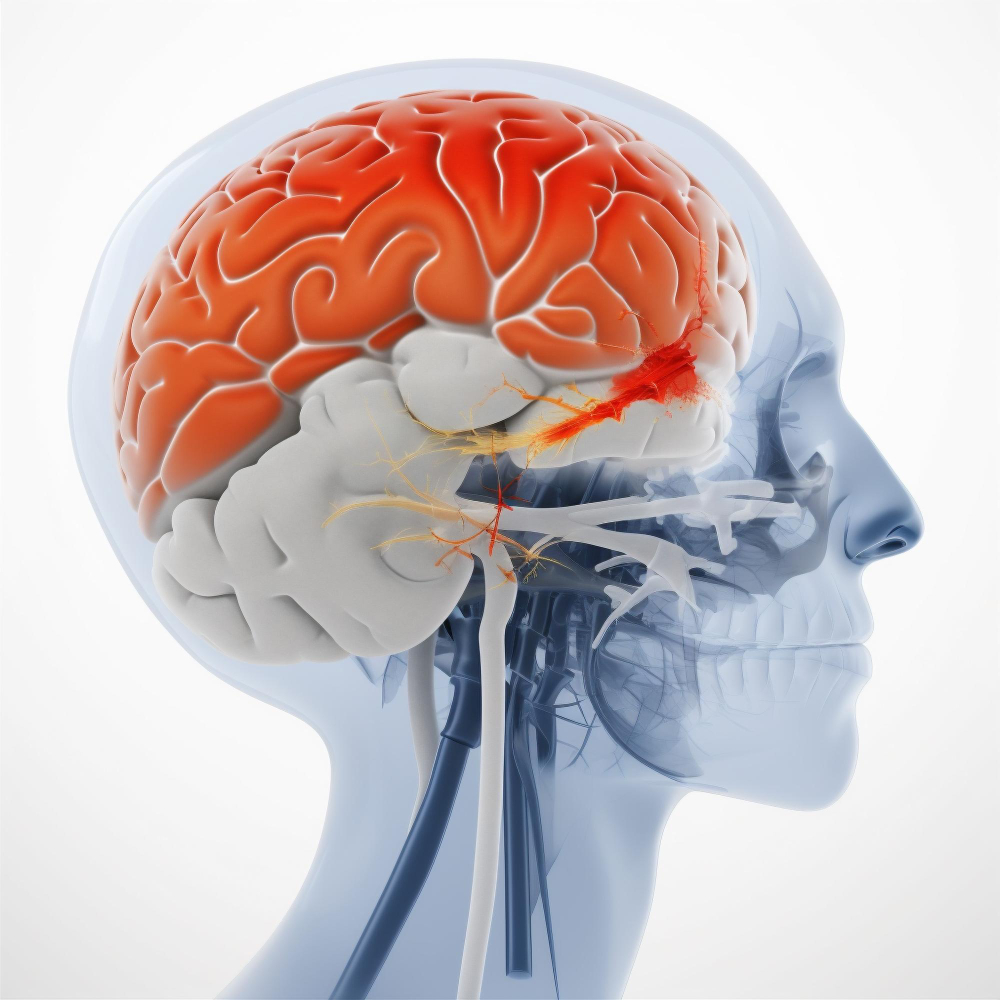

CT Scan, USG, 2D ECHO

Comprehensive imaging facilities for accurate and timely diagnosis.

High-Resolution CT Scanner